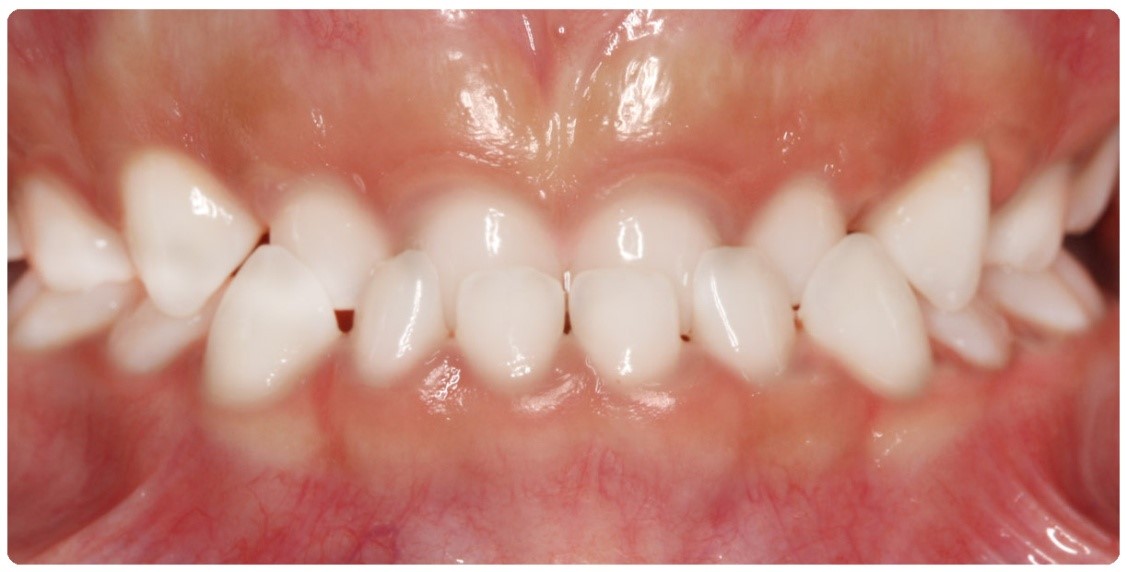

Vậy như thế nào là khớp cắn bình thường và khớp cắn lệch lạc? Đáng ngạc nhiên là không chỉ đơn thuần có một câu trả lời. Một khớp cắn bình thường được mô tả bằng những tiêu chí như: lý tưởng, phù hợp giải phẫu, mang tính trung bình, mang tính thẩm mỹ, hợp lý, đảm bảo chức năng cắn và khớp cắn không ảnh hưởng tới sức khỏe răng miệng. Do vậy, trên thực tế, cùng một vấn đề nhưng có thể có tồn tại nhiều hướng giải quyết khác nhau: điều trị hay không điều trị. Lệch lạc khớp cắn không phải là một bệnh nhưng là một biến thể khác so với tình trạng bình thường và có thể ảnh hưởng không tốt đến tình trạng sức khỏe răng miệng nói chung. Về cơ bản, có ba nguyên nhân chính dẫn tới việc cần phải tiến hành chỉnh nha: 1- Tình trạng, khấp khểnh, vẩu răng-hàm 2- Điều chỉnh chức năng ăn nhai của răng 3- Loại bỏ các nguy cơ có thể gây tổn hại tới sự khỏe mạnh lâu dài của răng và mô quanh răng.

Khớp cắn chéo quá sâu có thể tình cờ gây ra loét mô mềm, những trường hợp này nhu cầu thẩm mỹ thì nhỏ nhưng vấn đề loại bỏ nguyên nhân gây chấn thương mô mềm thì lớn. Ai nên được điều trị chỉnh nha? Phần lớn điều trị chỉnh nha được tiến hành vì nhu cầu thẩm mỹ và lợi ích mà mỗi bệnh nhân nhận được từ việc điều trị sẽ phụ thuộc vào mức độ trầm trọng của mức độ sai khớp cắn và nhận thức của bệnh nhân về vấn đề này. Một số cá nhân có thể có sự lệch lạc ở mức độ quá rõ ràng làm ảnh hưởng trầm trọng tới gương mặt của họ tuy nhiên họ cũng chẳng quan tâm đến và không cần điều trị nếu bác sỹ không có cách thuyết phục. Bác sĩ lâm sàng có thể đưa ra lời khuyên về phương pháp điều trị cho bệnh nhân nhưng cũng không nên yêu cầu họ một cách cứng nhắc mà nên để cho họ có thời gian ngồi lại và suy nghĩ để đưa ra quyết định cuối cùng hợp tác với bác sỹ điều trị. Lệch lạc khớp cắn mức độ nhẹ nên được điều trị với sự cẩn trọng vì khả năng tái phát sau khi điều trị. Các bậc phụ huynh có thể có rất nhiều yêu cầu khác nhau nhưng các bác sĩ lâm sàng nên tiếp cận những vấn đề này một cách cẩn trọng và chỉ tiến hành điều trị khi nó đem lại lợi ích tốt nhất cho bệnh nhân. Điều thiết yếu nhất cần nhớ là phụ huynh và bác sĩ cần phải nhận thức rõ về những hạn chế cũng như sự đòi hỏi nhiều thời gian của việc điều trị chỉnh nha. Kế hoạch điều trị nắn chỉnh răng Trong quá trình phát triển của bộ răng người, có thể chia làm ba giai đoạn chính như sau: giai đoạn răng sữa, giai đoạn răng hỗn hợp và giai đoạn răng vĩnh viễn. Sau đây là một số gợi ý những trường hợp nào cần và nên điều trị theo các giai đoạn của bộ răng: Kế hoạch điều trị ở hàm răng sữa Lý do điều trị: điều trị nắn chỉnh răng ở hàm răng sữa vì lý do sau: (1) loại bỏ các cản trở đến sự tăng trưởng bình thường của mặt và cung răng. (2) duy trì hoặc phục hồi lại chức năng bình thường Các trường hợp cần phải điều trị: a) Cắn chéo phía trước và sau.